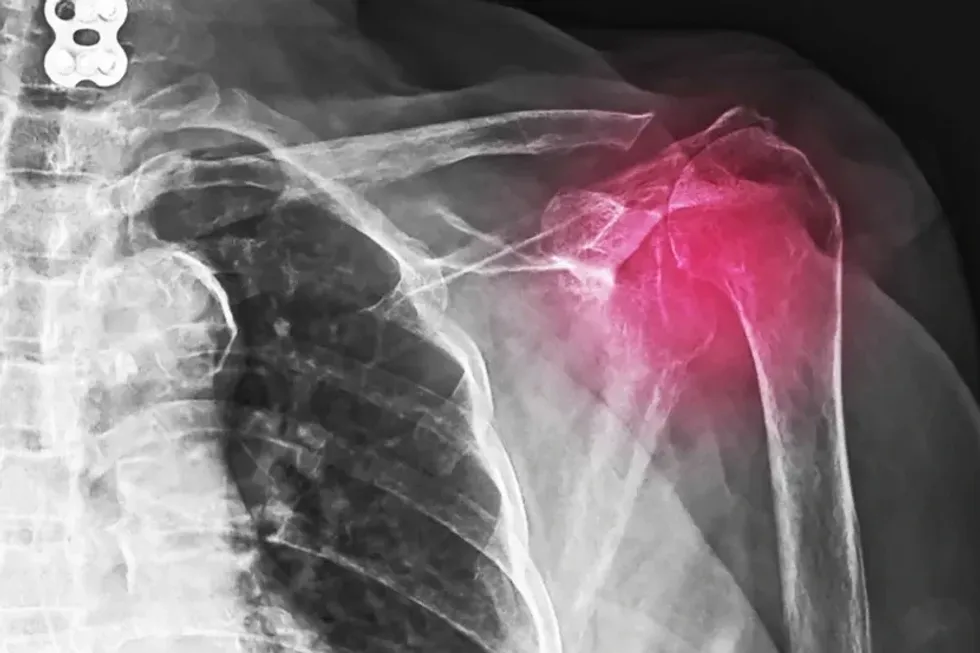

Shpatulla

Grumbullimi i kalciumit në tendinat e shpatullës mund të shkaktojë dhimbje dhe kufizim të lëvizjes. Kjo gjendje njihet si tendiniti kalcifikues dhe shpesh prek strukturat që stabilizojnë nyjën e shpatullës.